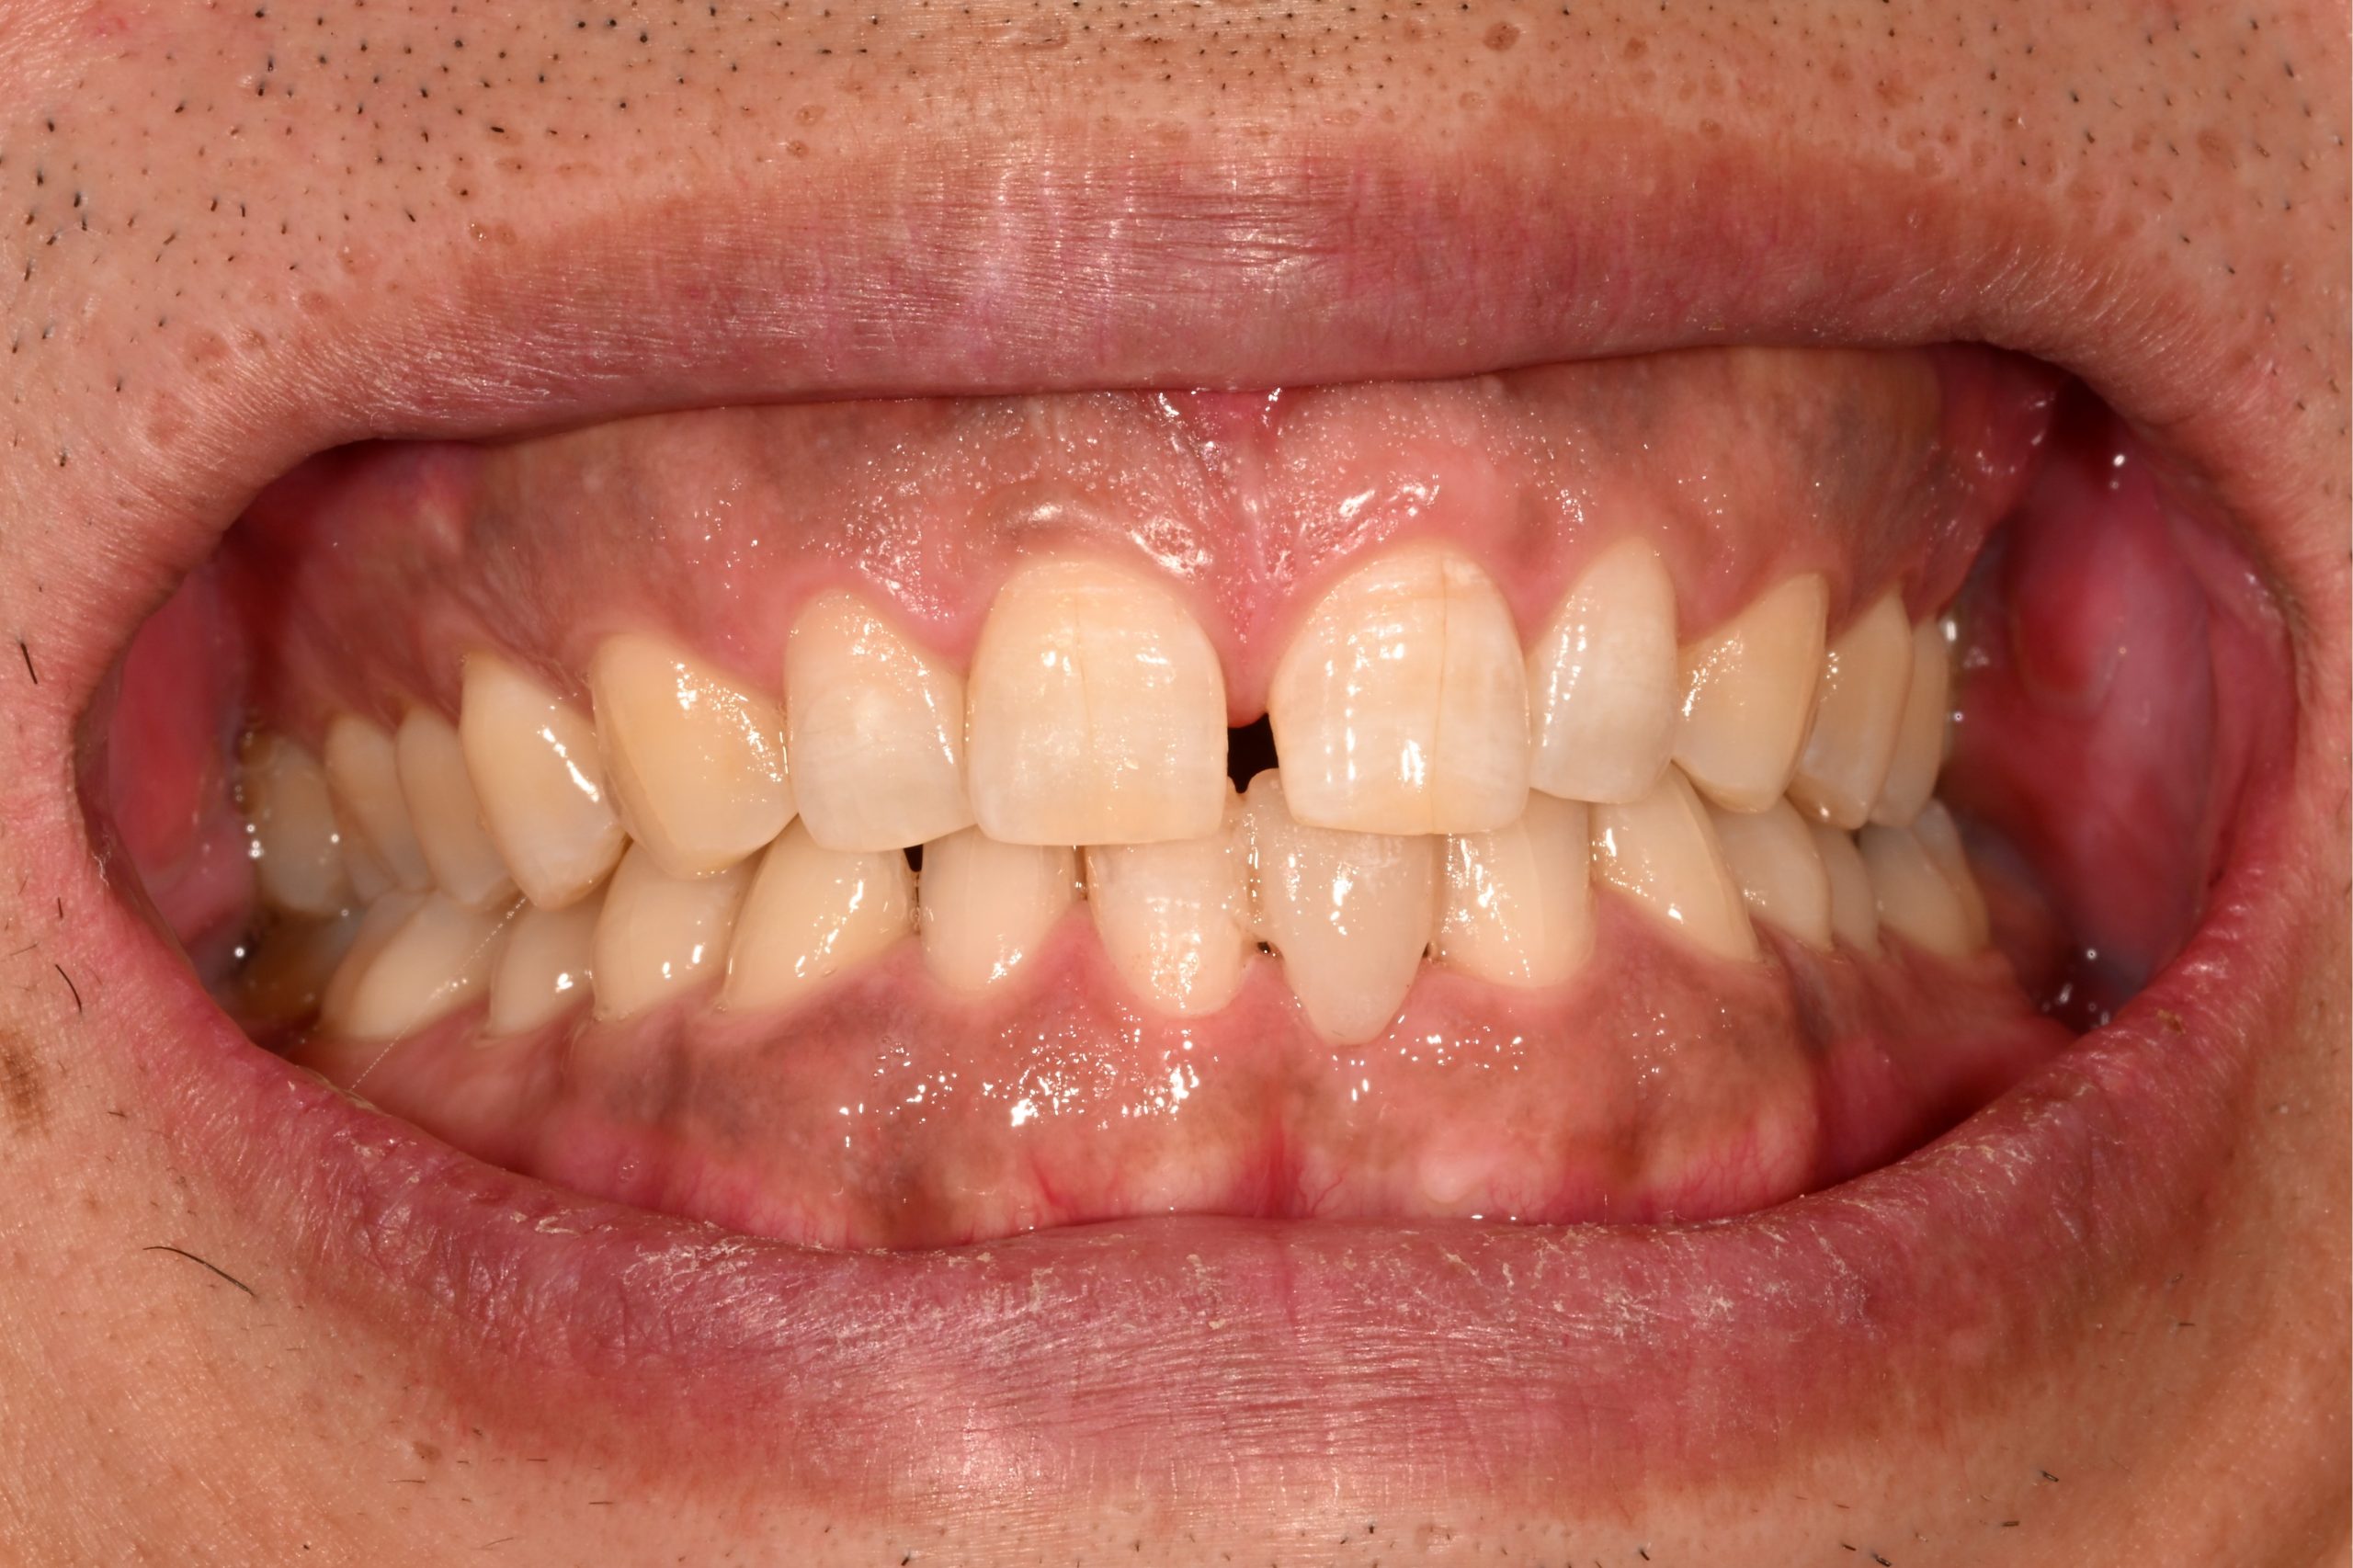

Before2

患者様の主訴

40代女性。横浜市在住。左上1番右上1番のクラウンに着色があり審美的に問題を抱えていたため、ご来院されました。

診断結果

ジルコニアクラウンを装着するために元のブリッジを外し、歯の形成を行いジルコニアクラウンをセット

治療内容

ジルコニアクラウンを装着するために元のクラウンを外し、歯の形成を行い光学印象(プライムスキャンによる)型取りを行いました。光学印象のデータを元に当院の院内技工室にてデジタル加工を行い、ジルコニアクラウンを作成し、セットを行いました。

治療期間

2回

治療費用

総額:330,000円(税込)

◼️内訳

ジルコニアクラウン(前歯):150,000円(税込)/1本×2本

光学印象(プライムスキャン)

リスク・副作用

補綴物の脱落・欠落、咬合違和感、色調補正